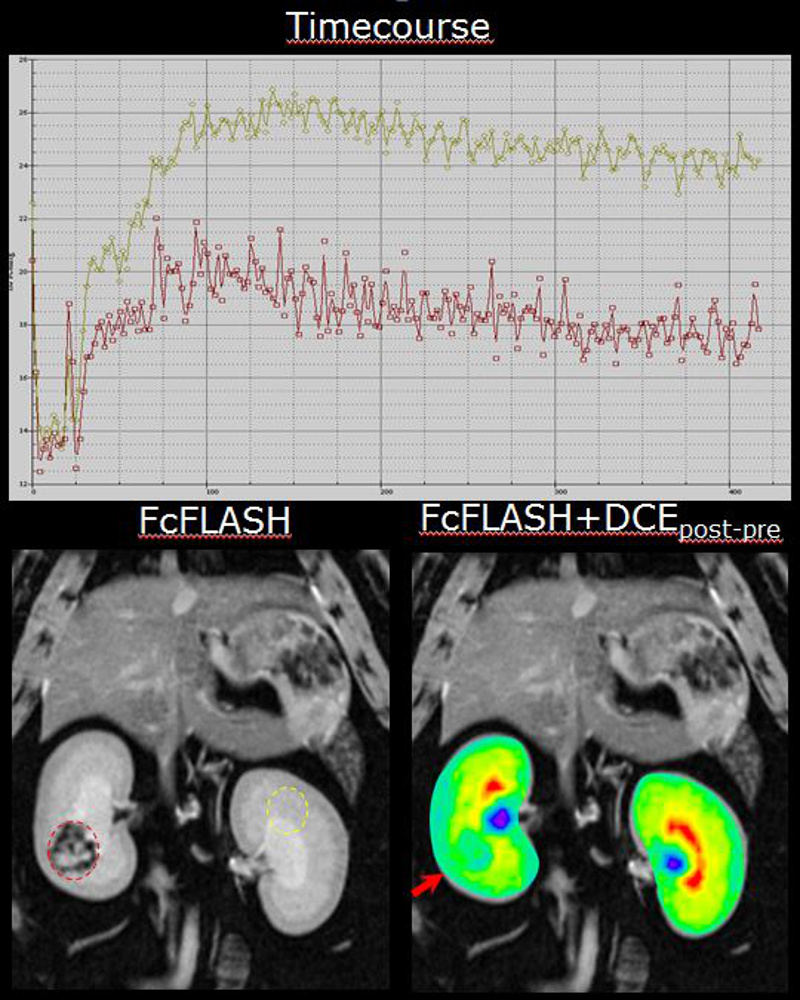

Dynamic Contrast Enhanced Imaging at 3T

72 mm rat body volume coil shows excellent homogeneity within deep tissues, allowing accurate time courses in Dynamic Contrast Enhanced studies